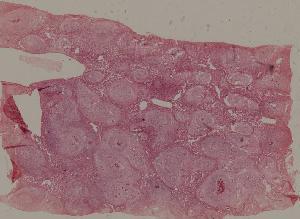

99.肝急性血吸虫病(兔)